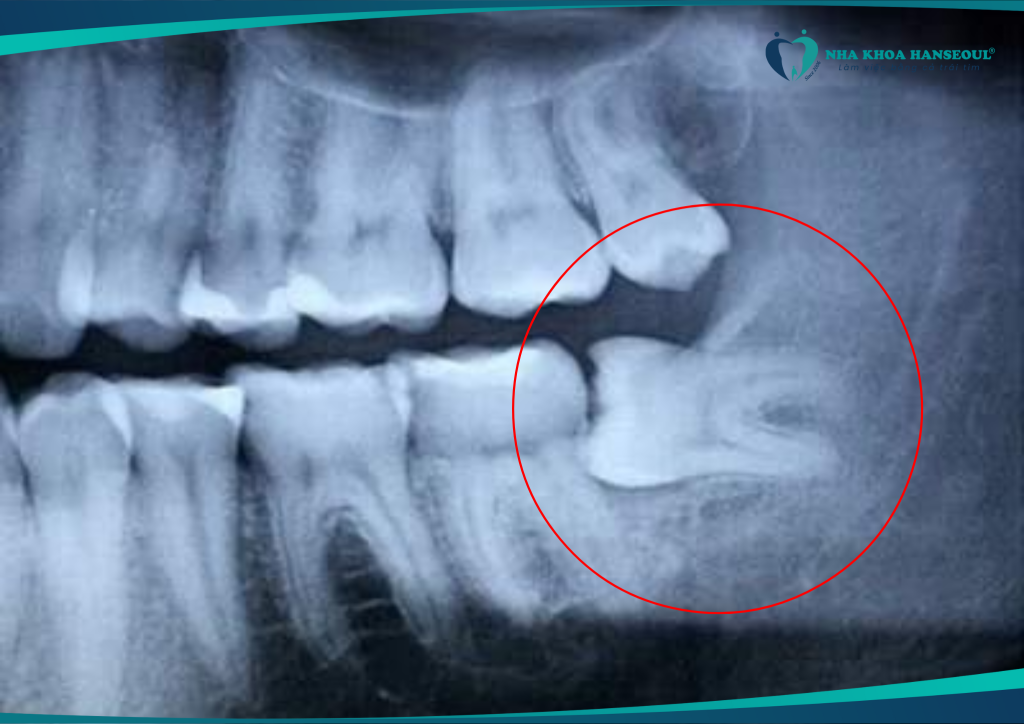

2 Tình trạng răng miệng trước khi điều trị: Răng số 8 mọc ngang, nhiều răng sâu ảnh hưởng thẩm mỹ

Tuấn Anh chia sẻ rằng anh gặp khá nhiều vấn đề về răng miệng trước khi đến với Hanseoul:

“Răng của em gặp khá nhiều vấn đề. Thứ nhất là răng 8 mọc ngang, gây đau nhức khó chịu. Bên cạnh đó còn có rất nhiều răng sâu, ví dụ như răng sâu trước cửa. Khi giao tiếp em khá ngại nở nụ cười, vì có răng sâu mà – nó làm ảnh hưởng đến thẩm mỹ.”

Tình trạng răng số 8 mọc lệch không chỉ gây đau âm ỉ mà còn ảnh hưởng thẩm mỹ và chức năng ăn nhai. Việc nhổ răng số 8 kịp thời giúp ngăn chặn biến chứng. (Ví dụ như viêm lợi trùm, sâu răng số 7 hay lệch khớp cắn).